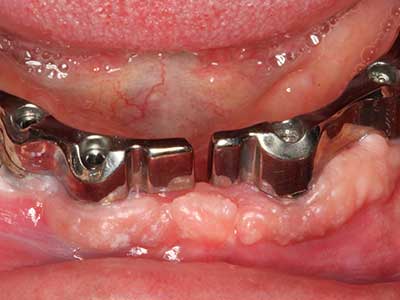

Special soft tips for peri-implantitis therapy are opening up new prospects in dentistry. They are the subject of current research and initial results are very promising.